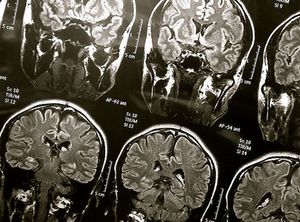

Sie sind hier: Startseite Nachrichten Gesundheit ARM bastelt an Chips für Gehirnimplantate Gehirn-Scans: Chip steckt bald direkt im Gehirn. Bild: flickr.com/wyinoue

Gehirn-Scans: Chip steckt bald direkt im Gehirn. Bild: flickr.com/wyinoue